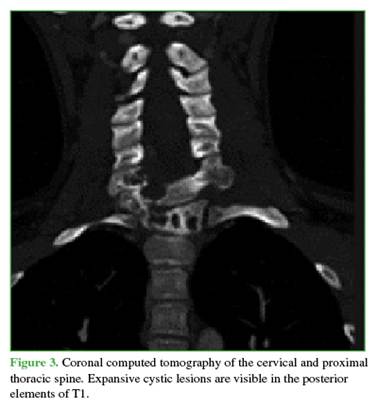

Complementary imaging revealed extensive vertebral involvement: at C7 (posterior arch), zones 4–7 and levels III and IV of the Weinstein-Boriani-Biagini (WBB) classification; at T1 (vertebral body), zones 10–3 and levels III and IV; and at T2 (right pedicle and posterior arch), zones 3–7 and levels III and IV.11 The lesions had an expansile cystic appearance (Figures 3 and 4). Due to the expansile nature of the lesion, a vertebral hemangioma was ruled out. The lesion was interpreted as an Enneking grade 3 ABC.